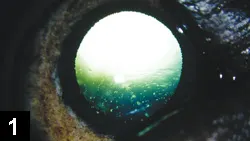

• Cataracts (Figure 1)

Figure 1. Hypocalcemic cataract in a dog with primary hypoparathyroidism (Courtesy Stuart Ellis, BVSc, CertVOphthal, MRCVS)